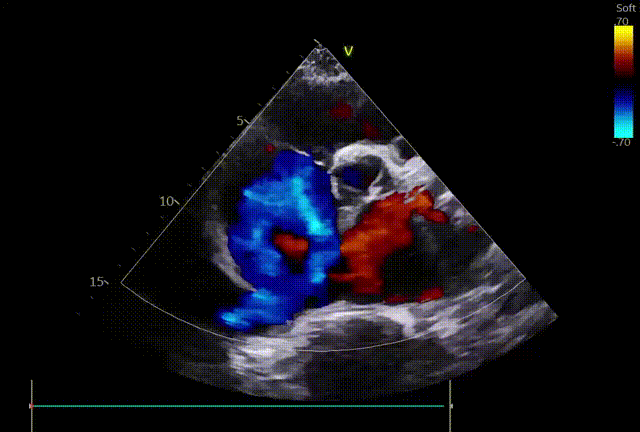

二尖瓣术前评估

复查TTE及TEE检查进一步评估二尖瓣情况。明确为FMR( Carpentier Ⅲb型),二尖瓣后叶栓系,2区瓣叶运动(视频2),重度FMR(4+), 肺静脉逆向血流;2区后叶长度1.15cm,2区前叶长度2.46cm,AP径3.2cm,瓣口面积5.1cm²,房间隔高度3.95cm,瓣叶无钙化,二尖瓣瓣膜条件适合行TEER手术。

图1、图2:2区瓣叶长度(前叶长度2.46cm,后叶长度1.15cm)及彩色血流